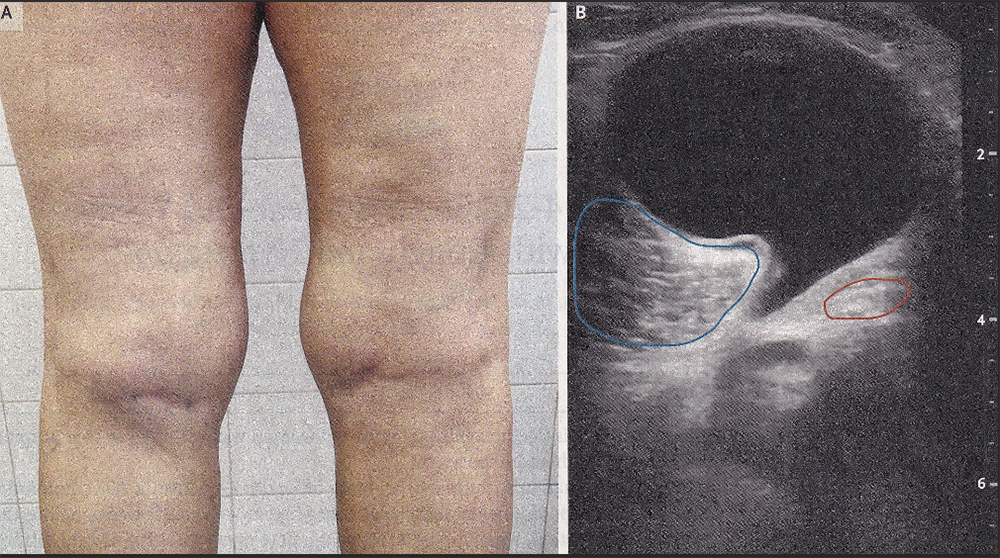

A 63-year-old woman with psoriatic arthritis involving her knees presented to the rheumatology clinic with a 9-month history of worsening left knee pain and swelling. Her psoriatic arthritis had recently been well controlled with leflunomide and monthly golimumab injections (both are immune system suppressants). Physical examination was notable for a nontender, palpable mass in the left popliteal fossa (back side of the knee) that was more prominent when the patient was standing with her knee fully extended (Panel A). A musculoskeletal ultrasound study done in the clinic (Panel B) showed a well-defined, anechoic, fluid-filled structure resembling a cartoon “speech bubble”, with a neck extending down into the joint space between the medial head of the gastrocnemius muscle (blue outline) and the semimembranosus tendon (red outline). A diagnosis of a Baker’s cyst was made.

A Baker’s cyst, also known as a popliteal synovial cyst, results when synovial fluid (joint-space fluid) seeps from the knee joint and flows into and accumulates into the gastrocnemius-semimembranosus bursa (sac). Baker’s cysts are associated with underlying joint disorders including osteoarthritis, traumatic injury, or inflammatory arthritis (as in this case). Imaging studies are not always needed to make the diagnosis but may be helpful to rule out other conditions. Ultrasound-guided aspiration of the cyst was performed, and an intracystic steroid injection was given. The patient’s knee pain abated shortly after treatment, and she remained pain-free as of the two-month follow-up. She will need regular follow-ups as the fluid can reaccumulate.